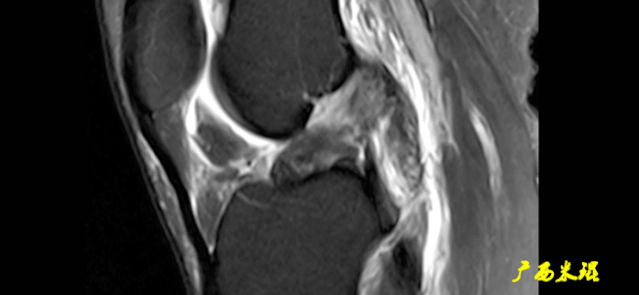

3)方向异常(ACL 下垂征):

-

有较完整的韧带低信号,但方向异常,呈下垂状。

一般见于股骨附着部的陈旧损伤,损伤的ACL下垂并粘附在PCL上。